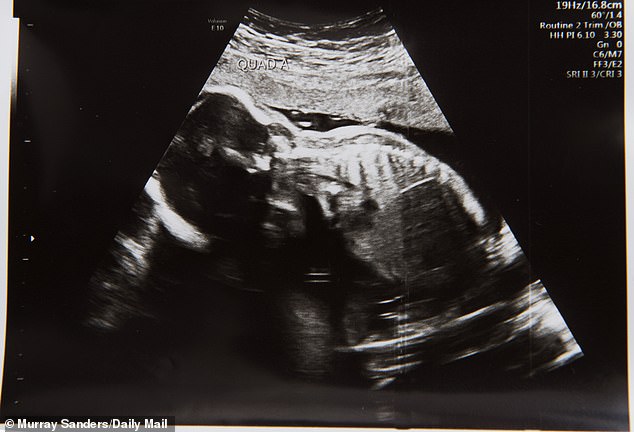

Pero cuando fue a la primera ecografía casi se desmaya cuando descubrieron que tenía a 4 bebés gestándose en su útero.

«Aunque me moría de ganas de ser madre, jamás ni en mis sueños más salvajes estuvo ser madre de cuatrillizos», dijo Tracey. Los médicos explicaron que tres de los óvulos fecundados se implantaron con éxito, pero uno luego se dividió y dio lugar a gemelas.